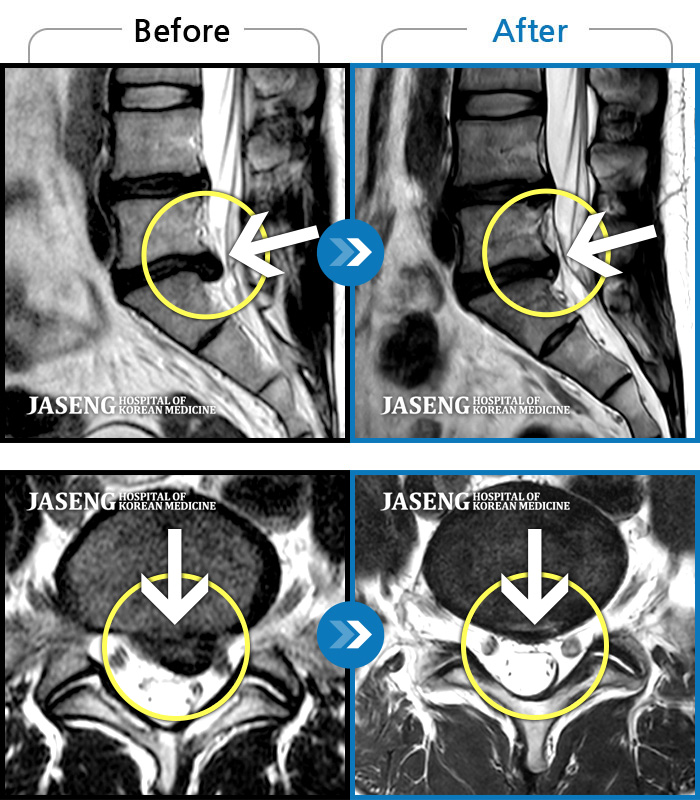

[뱸] 19.11.28~25.05.06

ȯںп Ǹ ǿ ԿǾ, ο ġ ۿ Ƿ ġḦ Ͻñ ٶϴ.